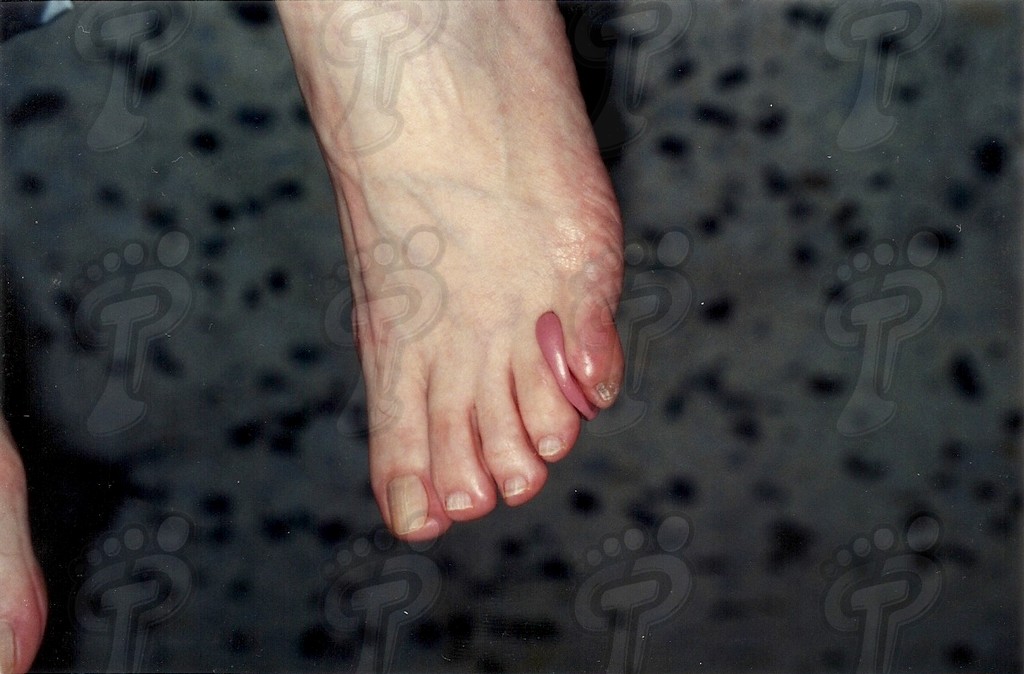

Denominamos exóstosis digital a la hipertrofia parcial circunscrita de la superficie de la falange de cualquier dedo. La exóstosis es una prolongación de la falange sin rotura del periostio y sin migración. Radiológicamente es unilateral, de configuración osteocartilaginosa, sin núcleo de osificación propio, radiopaca, y sin deferencia con el hueso adyacente. La exóstosis produce visualmente una hiperqueratosis distal o próxima a ésta, ya que entre la piel y la exóstosis no hay tejido suficiente para producir heloma. Las características de esta patología son:

- Recidiva de la lesión dérmica tras pocos días de su enucleación.

- Posterior a la deslaminación de la hiperqueratosis persiste dolor y molestias,

- Inflamación del tejido adiposo.

- Se aprecia una prominencia ósea en la zona dolorosa.